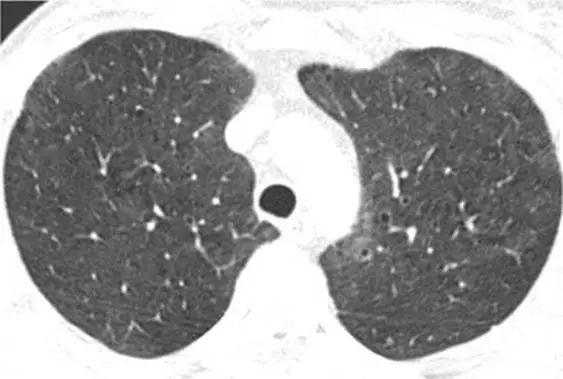

8、囊性病变

囊性模式由界限分明,圆形和外接空气的实质组成,有界限分明的壁和与正常肺。

经典疾病:淋巴管平滑肌肌瘤病(LAM),其特征是通常存在圆形的薄壁肺囊肿,没有在局部明显的特点,分布广泛,包括肋骨角和肺底。 LAM可能伴有胸水表现为胸膜胸腔积液。鉴别诊断是随机分布的囊肿,临床病史表现几乎只影响着育龄妇女。鉴别疾病:是肺组织细胞增生症、淋巴细胞性间质性肺炎(LIP)和小叶性肺气肿。

*LAM。上叶水平的HRCT表现出“囊性模式”,其特征是位于肺实质和隔中的许多大小不等的薄壁“真”囊腔的存在。

肺组织细胞增生症在处于纯囊性期(纯结节性和结节性-囊性期之后的第三期)时模拟LAM。它的特征是存在薄壁和厚壁的囊、形状呈异形,类似于苜蓿叶。囊肿具有特征性以上部和中部肺区分布为主。

*组织细胞增多症。上叶水平的HRCT揭示了一种“囊肿型”,其特征是许多薄或厚的“真”囊肿,形状奇异,大小不一。在右胸膜腔中发现引流导管以治疗气胸,这是这位27岁重度吸烟患者。